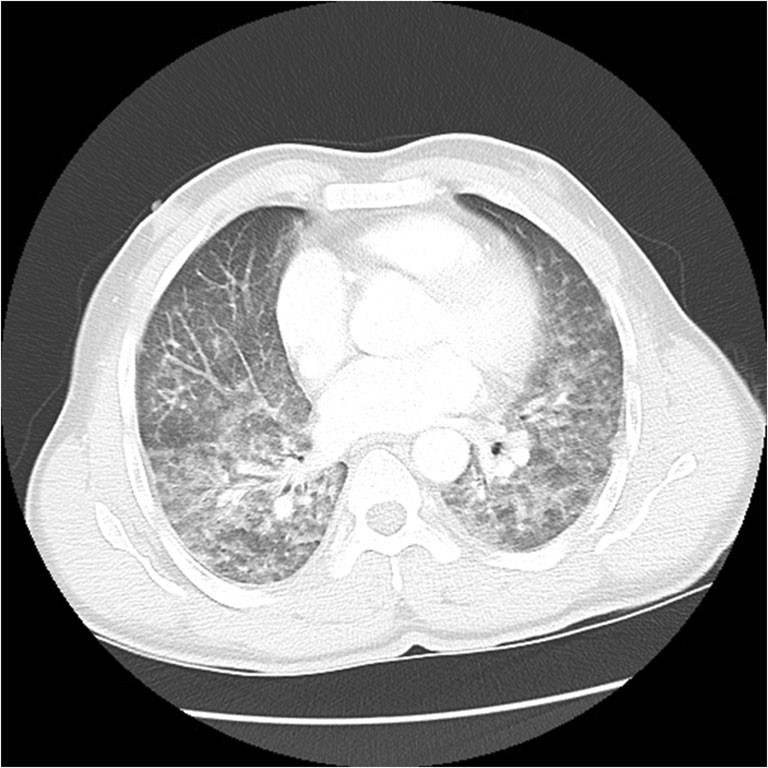

肺部感染ct图片,肺部感染胸片

35分胸部ct显示双肺下叶阴影,坠积性肺炎

治疗:普通肺部感染也有可能,鉴于外院口服阿莫西林无效,给予头孢曲松

新型冠状病毒型肺炎患者的ct表现

(3)时相特征:肺部病变性质随时间而改变.